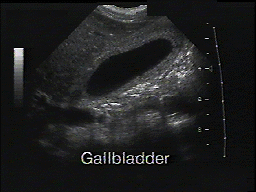

The image on the left shows a gallbladder with gallstones. The image on the right shows a normal gallbladder.